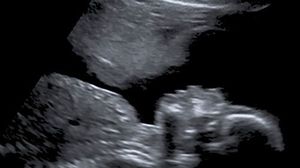

Minunea din pântecul unei femei! Ce a putut observa viitoare mamă la o banală ecografie: “Am privit și nu mi-a venit să cred”

O viitoare mamă a avut parte de surpriza vieții ei, în urma unei ecografii de rutină. Ce a observat femeia este de necrezut!

Totuși, la una dintre ecografiile de rurină, Stacey Astley a descoperit un detaliu care a lăsat-o fără cuvinte. Încă de când a aflat că este gravidă pentru a patra oară, femeia a suferit de anxietate, multiple sângerări, dar și alte probleme medicale. La împlinirea a 20 de săptămâni de sarcină, viitoarea mămică a fost la un control pentru o ecografie de rutină.

Au fost și alte incidente și alte sângerări, dar copilul era bine. Apoi, ca prin minune, problemele au dispărut. La următoarea ecografie a apărut chipul unui înger în imagine. Am privit și nu mi-a venit să cred, dar clar am simțit că am parte de protecție. Un înger păzitor se vede clar în această ecografie.”